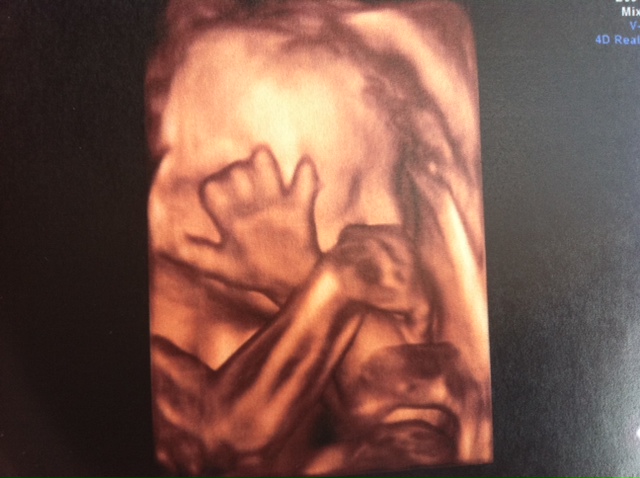

Here are a few of the recent pics (he was being a bit camera shy):